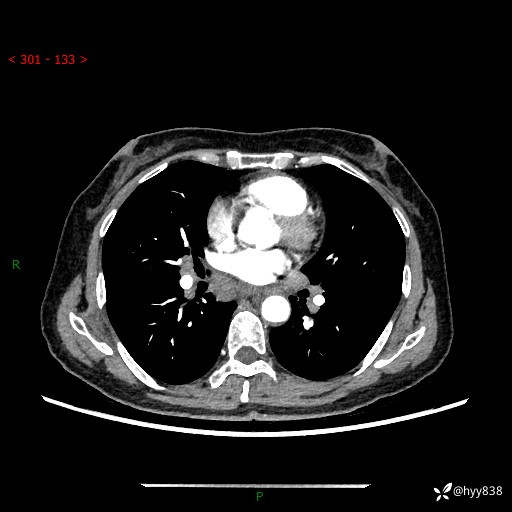

【患者信息】:58岁/女

【主诉】:体检发现肺结节

【检查】:胸部CT平扫+增强

结节病 (44)

小细胞癌 (19)